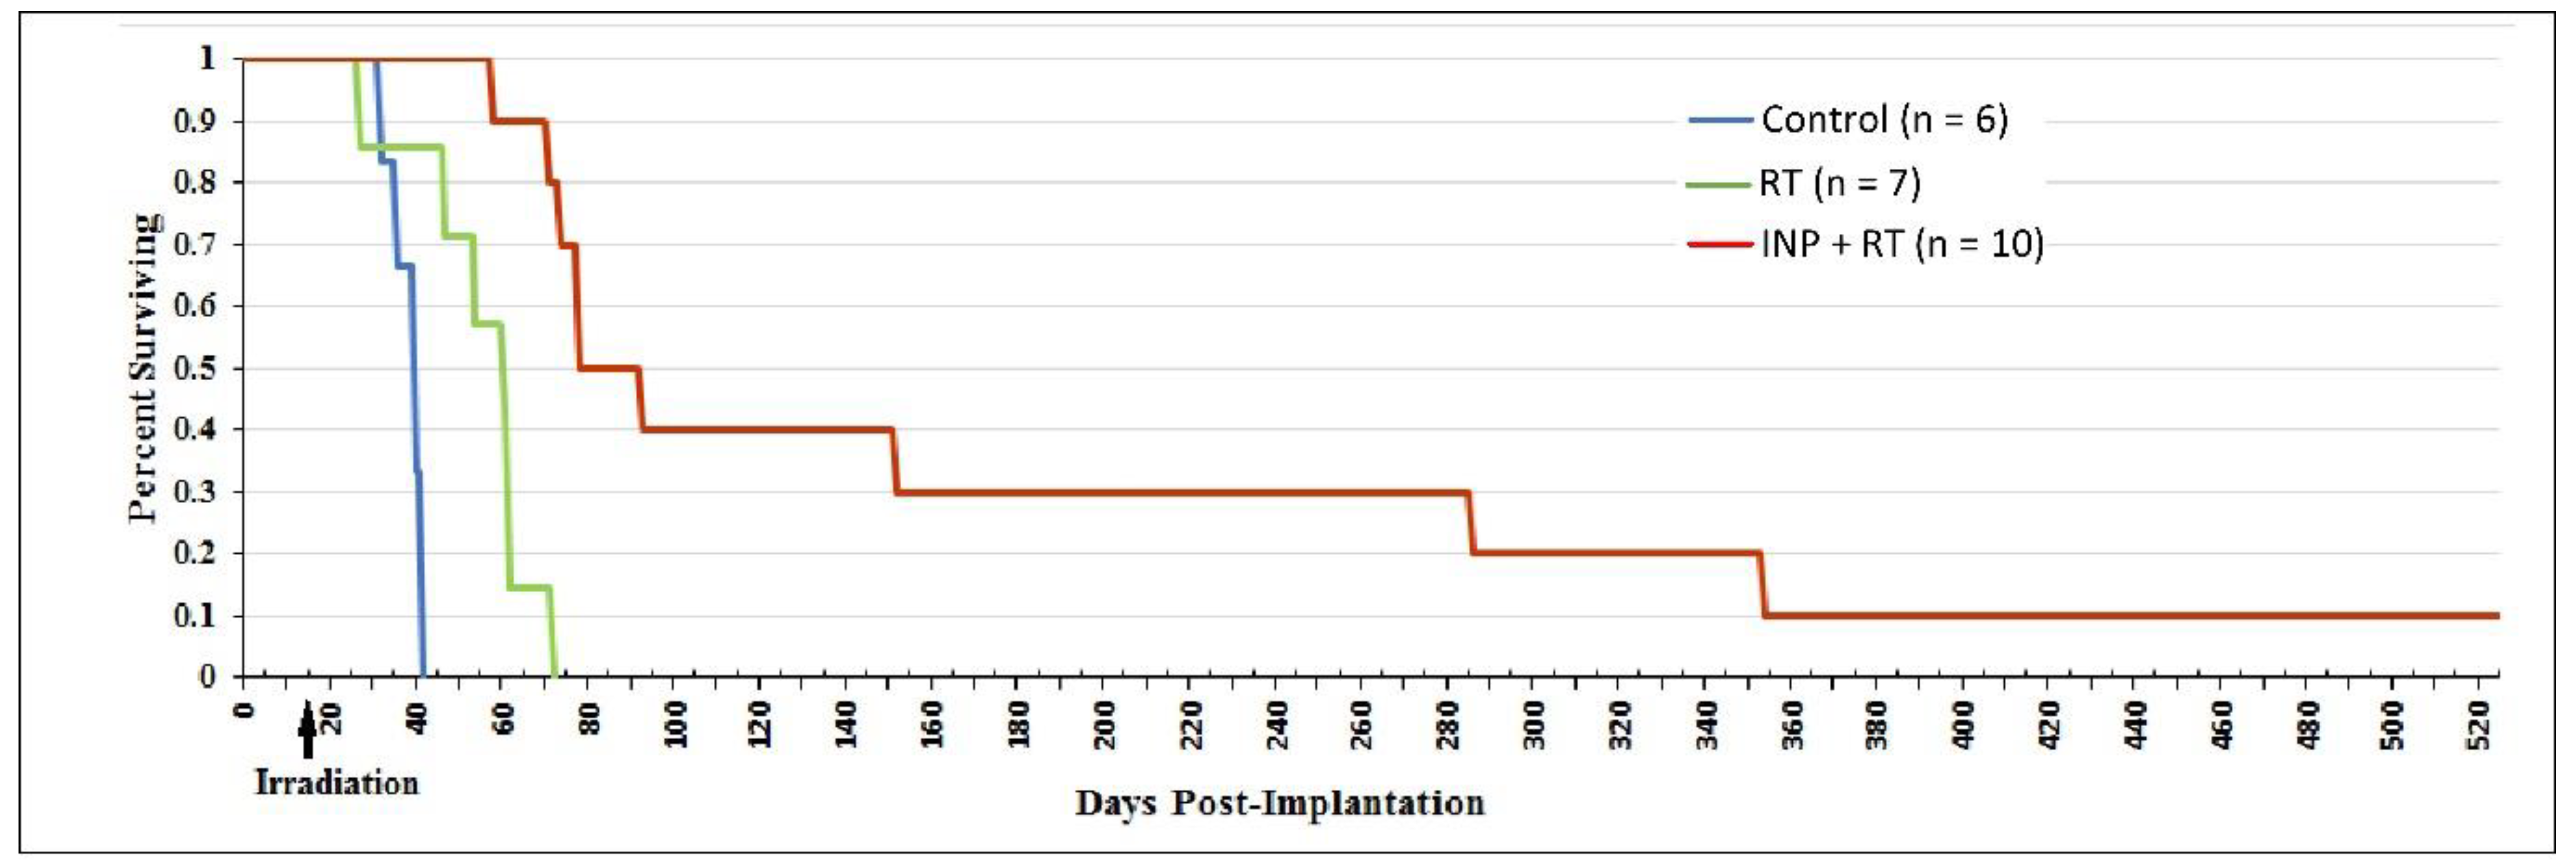

1.5. Iodine Nanoparticle Glioma Therapy

1.6. Iodine Nanoparticle Radiotherapy Synergy with Drugs